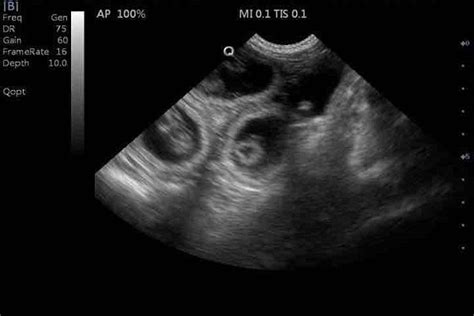

L'impianto degli embrioni nell'endometrio avviene con una distribuzione pressoché uniforme nei due corni uterini, generalmente tra i 17 e i 22 giorni dopo l'ovulazione e l'accoppiamento. A 21 giorni dall'accoppiamento, le membrane fetali piene di liquido formano nell'utero rigonfiamenti ovoidali distinti e separati, con un diametro medio di 12-15 mm.

In generale, per la cagna, si considera una durata di circa 65 giorni (con una variazione di circa 1 giorno) dal picco di LH (ormone luteinizzante). Le vescicole embrionali possono essere individuate ecograficamente già dal 18°-18° giorno e tramite palpazione transaddominale dal 20°-22° giorno. L'accuratezza di queste diagnosi aumenta con il progredire della gestazione. La palpazione manuale può essere effettuata dal 25° al 30° giorno dall'ovulazione, quando le vescicole sono percepite come rotondeggianti con un diametro di circa 4-5 cm. Ecograficamente, è consigliabile attendere fino al 26°-28° giorno dall'ovulazione per una maggiore accuratezza.